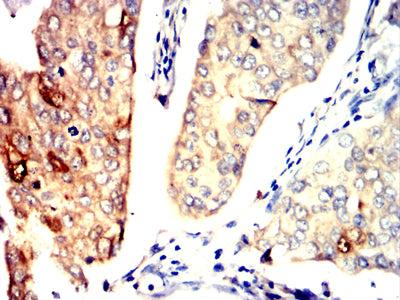

Immunohistochemical analysis of paraffin-embedded human breast cancer tissues using PPID mouse mAb with DAB staining.